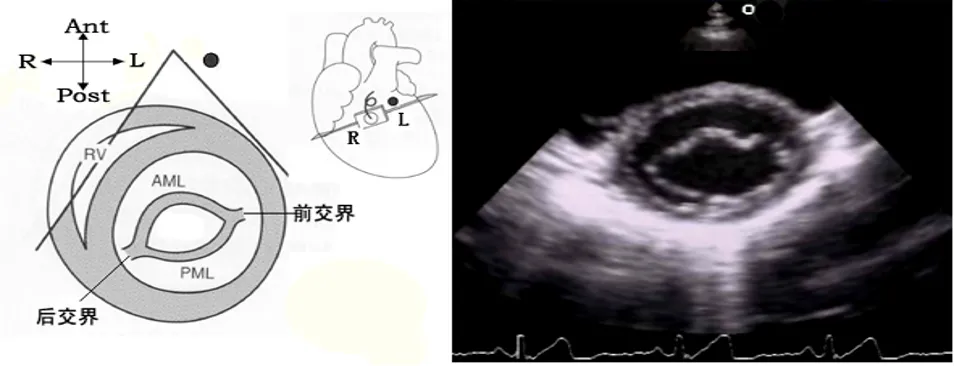

05

胸骨旁二尖瓣口水平短轴切面

● 探头位置:探头置于胸骨左缘3、4肋间,声速恰好通过二尖瓣口。

● 观察内容

1:瓣膜活动:二尖瓣形态结构,活动和测量二尖瓣瓣口面积。

2:室壁厚度:基底部整个左室壁。

3:室壁活动:基底部整个左室壁。